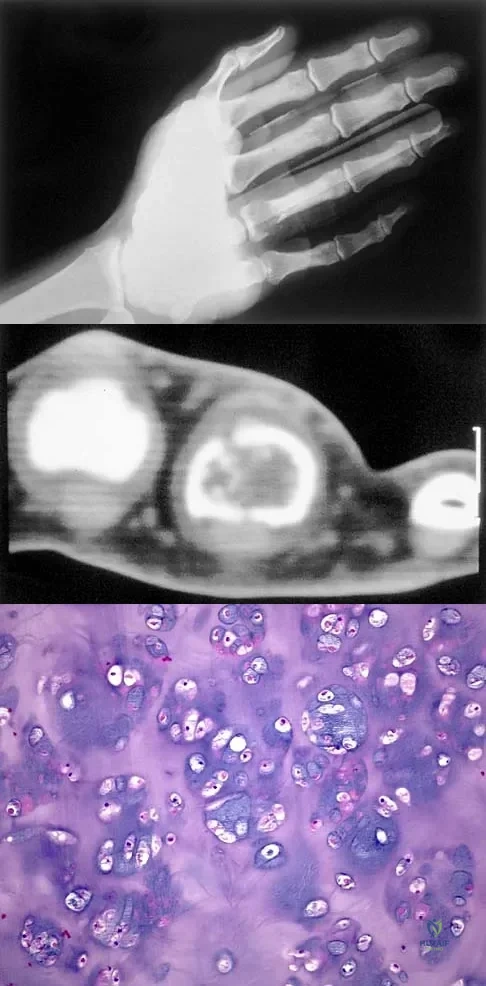

A 10-year-old boy has a painful thigh mass. A radiograph, MRI scan, and biopsy specimen are shown in Figures 42a through 42c. What is the most likely diagnosis?

Explanation